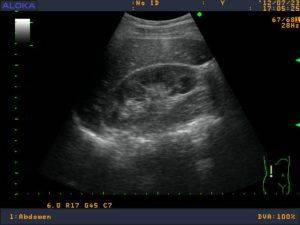

УЗИ безболезненный метод без побочных эффектов и особых противопоказаний. Позволяет выявить нефрологические патологии в почках на ранних стадиях. Людям из группы риска рекомендуется проходить УЗИ почек ежегодно. С помощью 20-ти минутного обследования врач может оценить визуально: общий вид и структуру почки, ее размеры, наличие конкрементов, кистозных и опухолевых образований, обнаружить видимые отклонения от нормы.

- Эхогенность характеризует структуру почек, плотность ее тканей. Ткани отражают ультразвук (используемый при УЗИ) по-разному. При высокой плотности тканей изображение на мониторе светлее, низкой плотности – темнее. Эхогенность используется для оценки структуры любых органов.

Сравнивая данные пациента с нормой (эхогенностью здоровой однородной ткани), медицинский специалист определяет однородные и неоднородные участки тканей исследуемого органа. Повышенная эхогенность наблюдается при склеротических процессах в органе, гломерулонефрите, хроническом пиелонефрите, диабетической нефропатии и амилоидозе.

При обследовании структуры паренхимы используют понятие эхогенности. Эхогенность здоровой ткани органа однородная. Гипоэхогенность описывает структуру, темнее окружающих тканей. Гиперэхогенное образование на мониторе отображается как белое пятно. Выделяют однородную гиперэхогенность и неоднородную, когда существует чередование нормальной ткани и ткани с повышенной эхогенностью.

Мочекаменная болезнь

Возможно обнаружить различные камни в почках с помощью УЗИ, которые визуализируются в качестве гиперэхогенных (то есть более ярких, чем сама ткань почки) образований округлой или овальной формы с анэхогенной дорожкой. Находясь в чашечно-лоханочной системе, они могут перемещаться относительно друг друга. Кроме того, врач-диагност должен установить их количество, размеры и расположение.

Кисты и опухоли

Объемные новообразования. Кисты различной этиологии определяются в виде округлых объемных образований с ровными и четкими контурами, имеющих анэхогенную внутреннюю структуру и дистальное усиление ультразвука. Доброкачественные опухоли имеют однородную гиперэхогенную эхоструктуру, ровный контур и округлую форму. Злокачественных же отличает неровность контура, вплоть до его размытия, и неоднородность структуры. Появление эхонегативных участков в опухоли свидетельствует о наличии в ней кровоизлияний или очагов некроза.